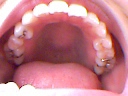

私は開咬です。たぶん左右一番奥の歯しか噛んでません…小さい頃から指しゃぶりが治らず、夜寝る時は小学校高学年までやっていた気がします。また舌癖?がある?話す時、舌が前にでる(舌ったらず)です。

写真を拝見した感じでは、矯正治療のみで可能と思われます。(当院ホームページー永久歯開咬参照)